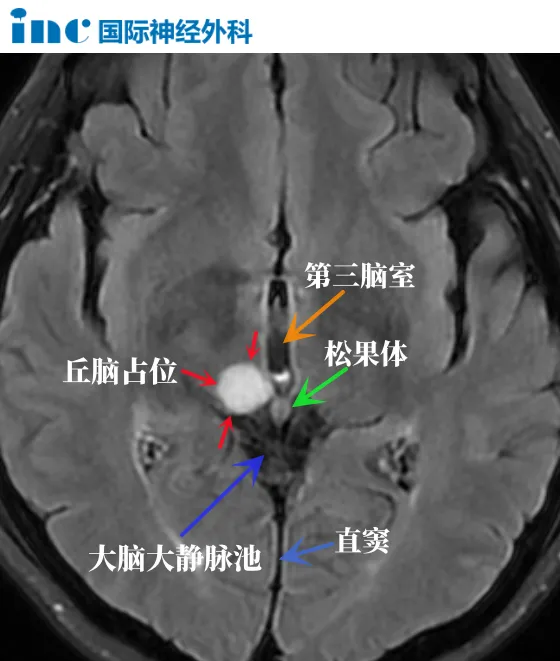

丘脑位置示意

位置深

丘脑是脑部较深在的区域,其前下方则毗邻下丘脑及中脑,约50%的丘脑表面被内囊所覆盖。手术难度较大,肿瘤切除时如损伤周围重要结构,将导致不良后果。

丘脑周围包括四个重要的游离间隙(free surface),Yasargil将丘脑的四个游离面分为侧脑室面、脉络膜面、三脑室面及四叠体池面,每一个游离面都能通过经侧脑室入路或经四叠体池入路达到。这样的不同毗邻关系使丘脑手术入路的选择重要。

丘脑附近重要的邻居有松果体、下丘脑、中脑。

邻居一:松果体

松果体控制着人体的睡眠与觉醒、情绪、智力。